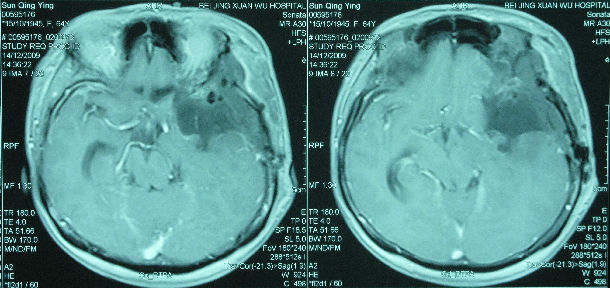

左侧蝶骨嵴巨大脑膜瘤切除根治